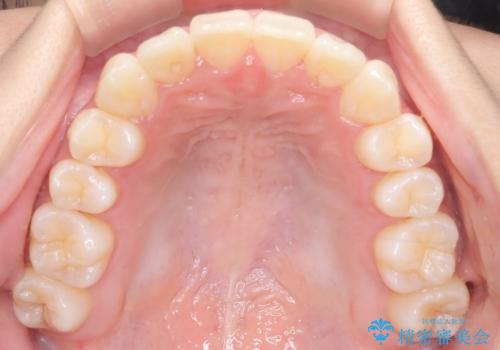

前歯の叢生・Ⅱ級咬合を改善|TADを用いた遠心移動+インビザライン矯正

- 前歯のガタガタと臼歯関係のⅡ級(上顎の歯列が前方にある状態)を改善するため、TAD(歯科矯正用アンカースクリュー)を使用したインビザライン矯正を計画しました。まずTADを上顎の適切な位置に設置し、それを固定源にして奥歯を後方(遠心)へ移動させ、十分なスペースを確保します。その後、インビザラインによるマウスピース矯正で前歯の歯列を整え、臼歯関係を正常化します。治療期間はおよそ1年半〜2年を想定しています。

前歯部の叢生(ガタガタ)と臼歯関係のズレを改善するため、抜歯をせずに奥歯を後方へ移動(遠心移動)させることを選択しました。TADという小型のアンカースクリューを顎骨に設置することで、確実かつ効率的に奥歯を後方へ移動させました。併せて透明で目立ちにくいインビザラインを用いることで、審美性を保ちながら治療を進めることが可能でした。患者様の負担が少ないマウスピース矯正と固定源のTADを組み合わせることで、抜歯することなく歯並びと噛み合わせを大幅に改善でき、大変ご満足いただけました。